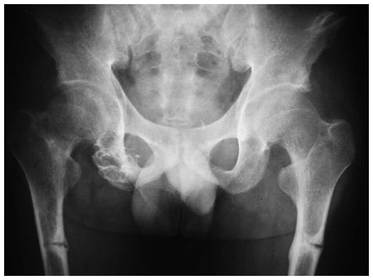

1815 What characteristic x-ray finding in osteomalacia is shown? Looser's pseudo #'s. Seen here in both femurs. K & C p559.